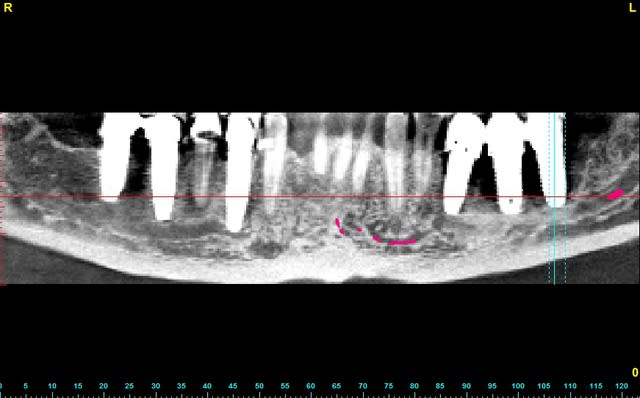

le cas n'est déjà pas facile...

il faut explanter tous le secteur 3 et 4

mais quid de la gestion osseuse ?

Précision : le nerf est à fleur des implants il est primordial d'être prudent lors de l'explantation.

Rien que parce que le nerf lingual a une chance sur 2 d' être en lingual des apex implants à déposer, c'est de la chir maxillo.